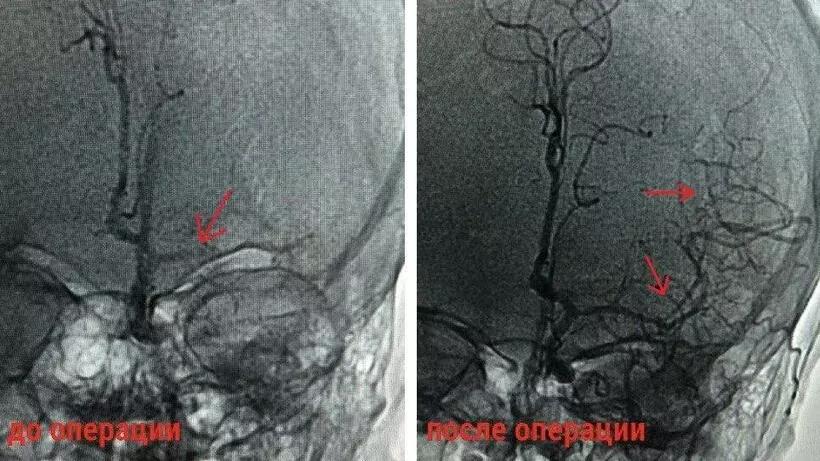

«Под рентген-контролем врачи провели тромбоэкстракцию – извлечение тромба из артерии головного мозга, что позволило специалистам восстановить кровоток. Операция прошла успешно», – рассказал заведующий отделением рентгенохирургических методов диагностики и лечения Леонид Гинзбург.

У пациентки наблюдались речевые нарушения, а также паралич всей правой стороны. После проведенного обследования врачи подтвердили диагноз.